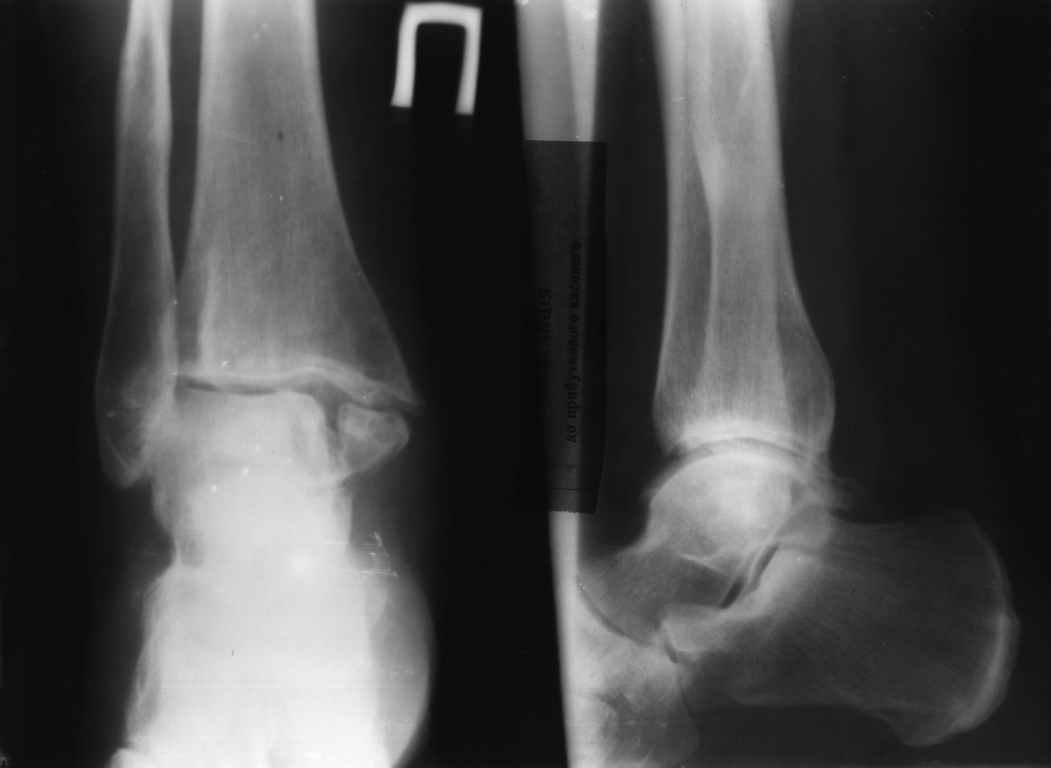

На представленных снимках определяется несросшийся перелом внутренней лодыжки и, возможно, частичное повреждение синдесмоза-для уточения степени повреждения-сравнительная рентгенограмма с нагрузкой.Честно говоря возникает вопрос-что делала пациентка в течение 5 лет после травмы?

Удивительно видеть сохранившееся суставное пространство после 5 лет дисконгруэнтности суставных поверхностей.

Не думаю, что оснвная проблема связана с несращением внутренней лодыжки, скорее всего она комплексная: поврежденный синдесмоз, суставная

дисконгруэнтность, несрещение вн.лодыжки.